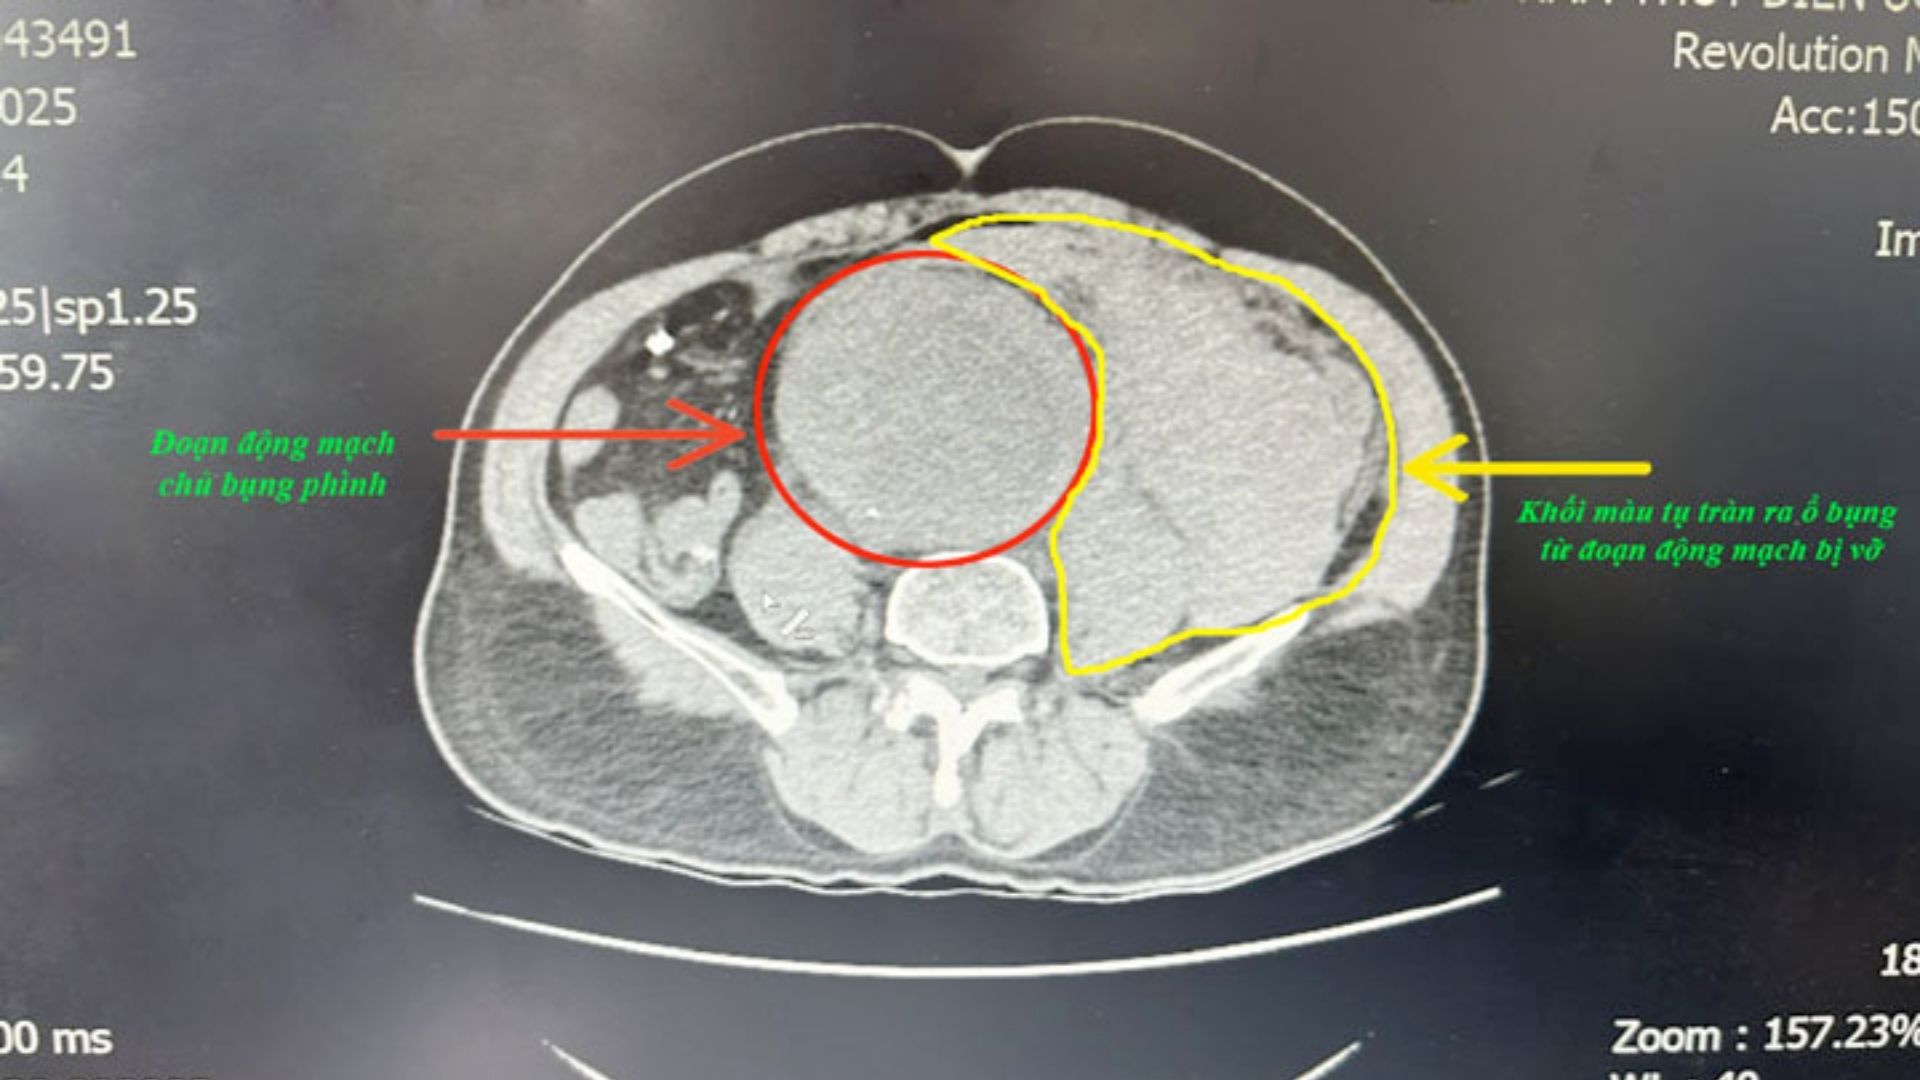

Trước đó, ông N.B.K. đang ở nhà thì xuất hiện cơn đau bụng dữ dội, khó thở, mệt lả, được gia đình đưa đến bệnh viện cấp cứu. Tại Khoa Cấp cứu - Bệnh viện Việt Nam - Thụy Điển Uông Bí, người bệnh có dấu hiệu choáng nặng, đau bụng dữ dội, da xanh nhợt, không bắt được mạch, huyết áp không đo được. Kết quả chụp CT cho thấy túi phình động mạch chủ bụng đoạn dưới thận lan đến động mạch chậu hai bên đã vỡ, gây tụ máu lớn sau phúc mạc.

Ngay lập tức, Bệnh viện kích hoạt quy trình “báo động đỏ nội viện”. Kíp phẫu thuật, gây mê, truyền máu được huy động khẩn cấp. Người bệnh vừa được truyền máu, dùng thuốc vận mạch, vừa được mổ cấp cứu. Trong quá trình phẫu thuật, các bác sĩ ghi nhận có khoảng 2.000ml máu trong ổ bụng cùng một vết rách lớn ở thành động mạch chủ. Ekip đã nhanh chóng kẹp động mạch chủ trên và dưới vị trí vỡ, sau đó thay thế đoạn mạch tổn thương bằng mạch máu nhân tạo.